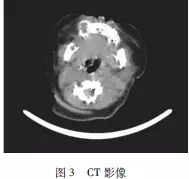

患者,男,3個(gè)月。2周前于右上牙區(qū)發(fā)現(xiàn)紅豆大小腫物,考慮“馬牙”未予重視?,F(xiàn)發(fā)現(xiàn)腫物呈黃豆大,遂來我院就診。體查:右上唇至右眶下孔處隆起明顯(圖1),右上頜骨處有一半球形腫物,向頰側(cè)膨隆,約蠶豆大小,呈淺藍(lán)色,界清,表面無紅腫破潰,質(zhì)硬,不活動(dòng)(圖2)。下頜下淋巴結(jié)未及腫大。外院CT示:右上頜骨占位,懷疑成釉細(xì)胞瘤”(圖3)。